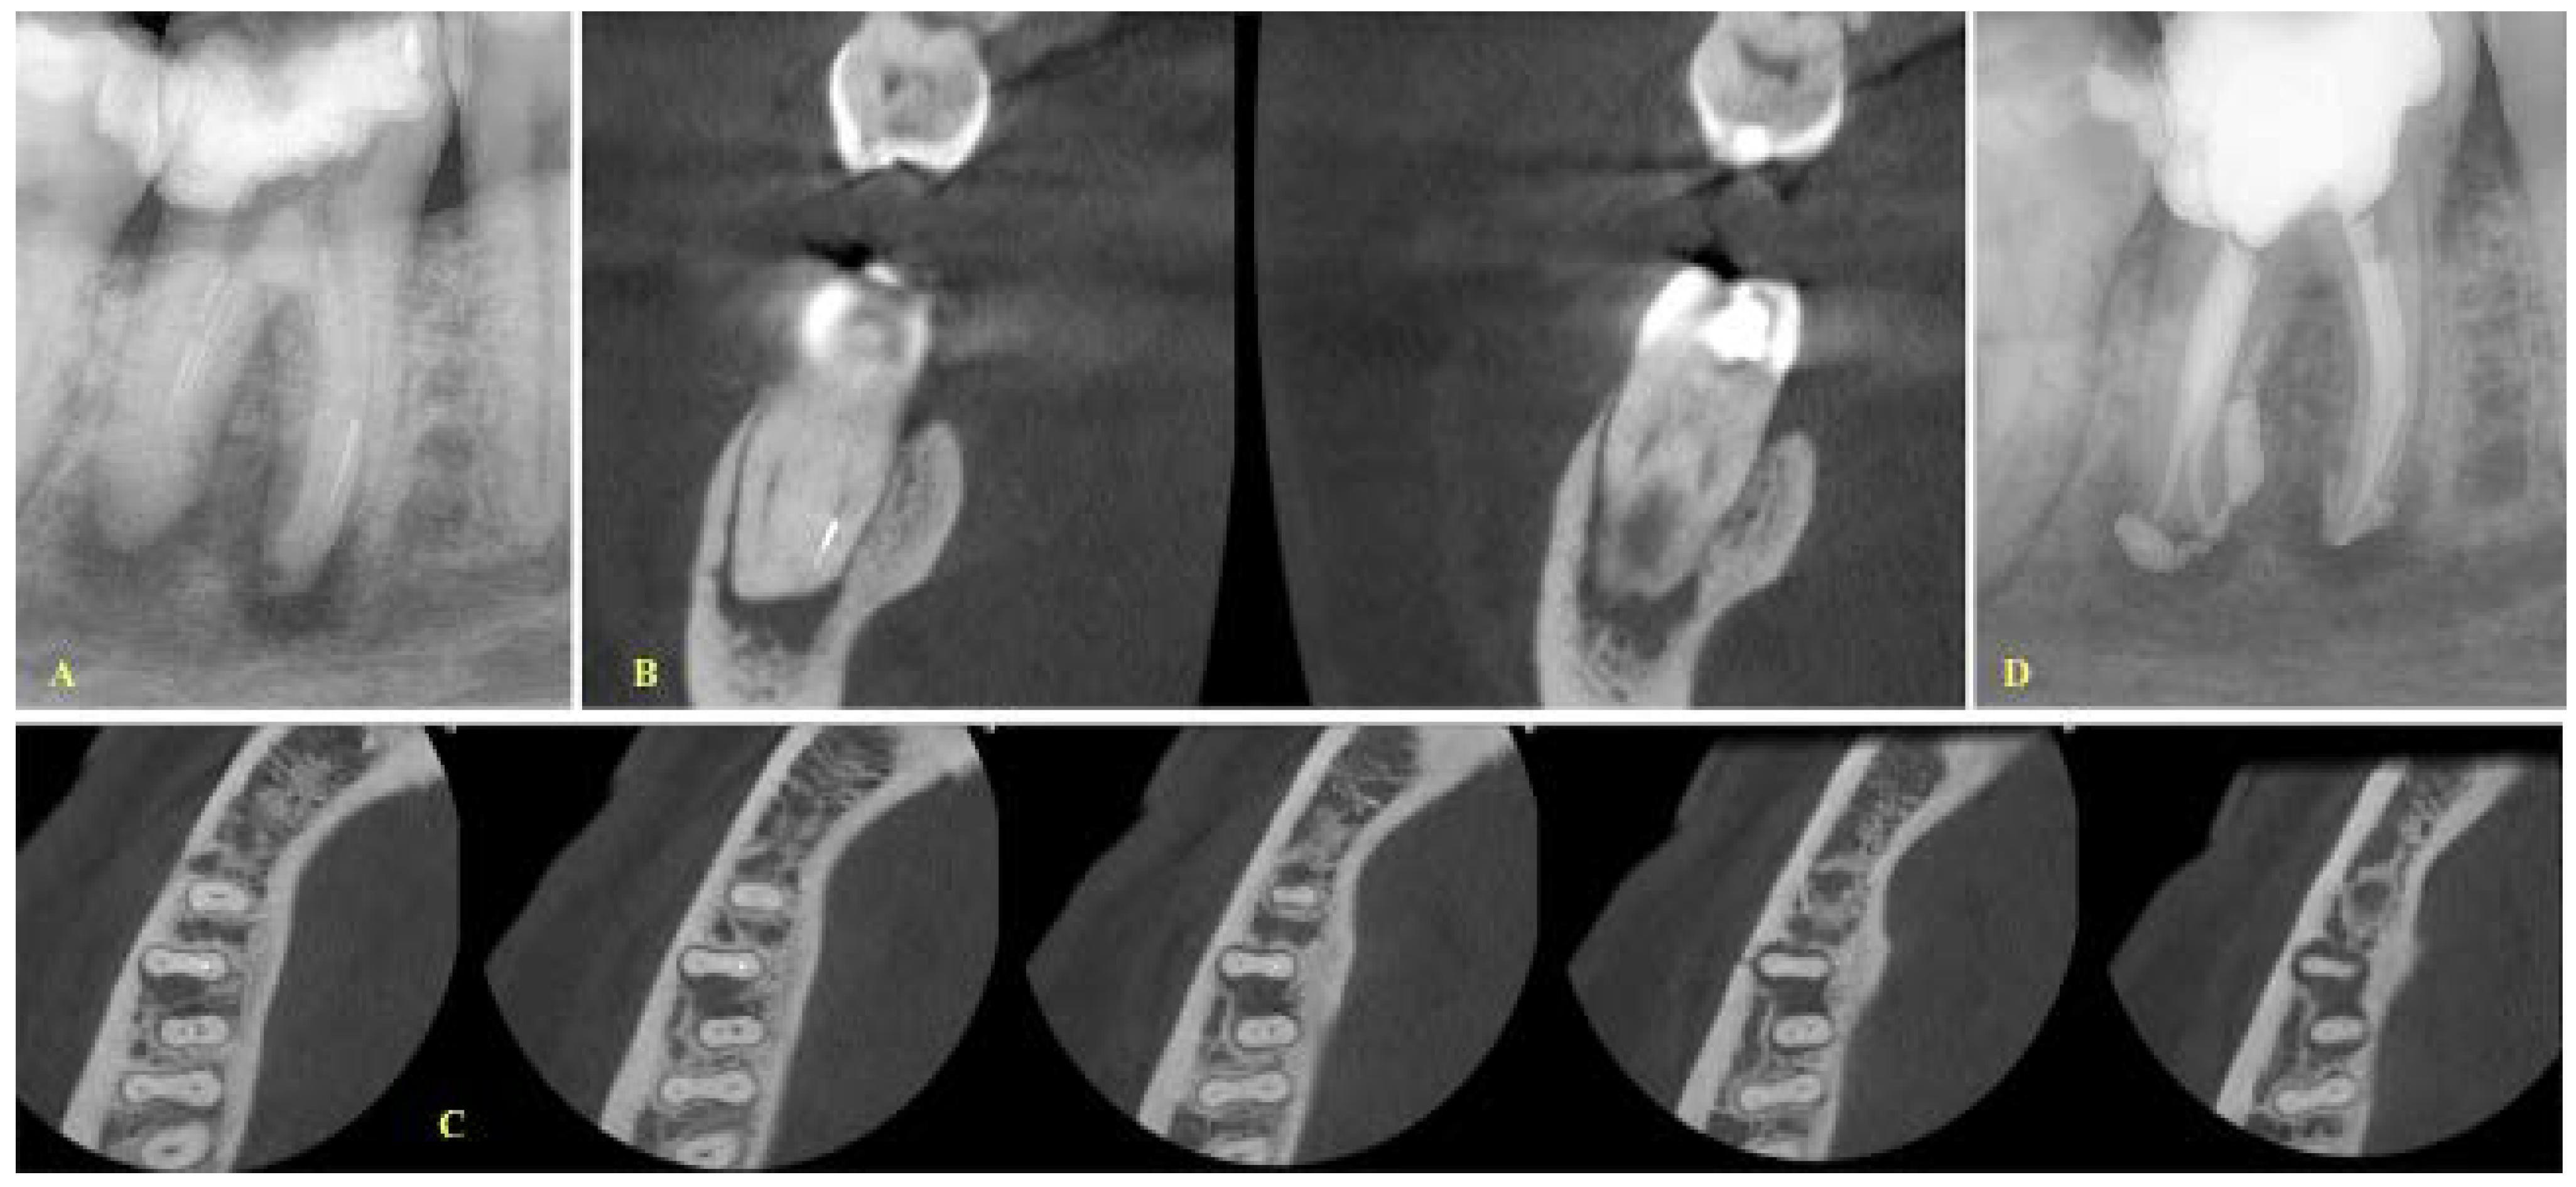

- If a lesion was present, the canals were separate and the fragment was located at the apical level, and a final treatment plan of bypassing the fragment was set (Figure 1).